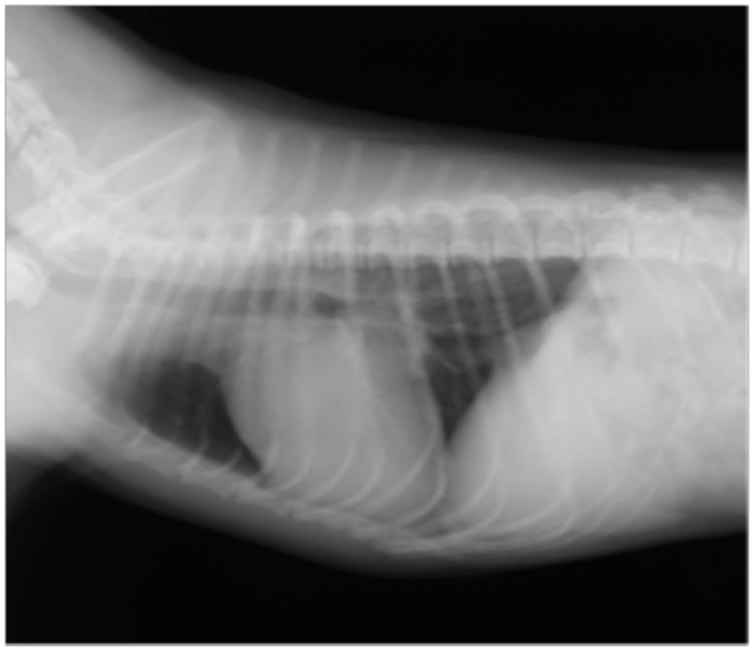

症例1:【マルチーズ 12歳齢 去勢オス】

B:胸部レントゲン写真 側面像

胸部レントゲン検査において重度の心拡大と肺水腫が認められた。超音波検査では、重度の僧帽弁閉鎖不全症、三尖弁閉鎖不全症、中程度の大動脈弁閉鎖不全症を合併していることが判明した。三尖弁逆流速度から肺高血圧症が示唆された。